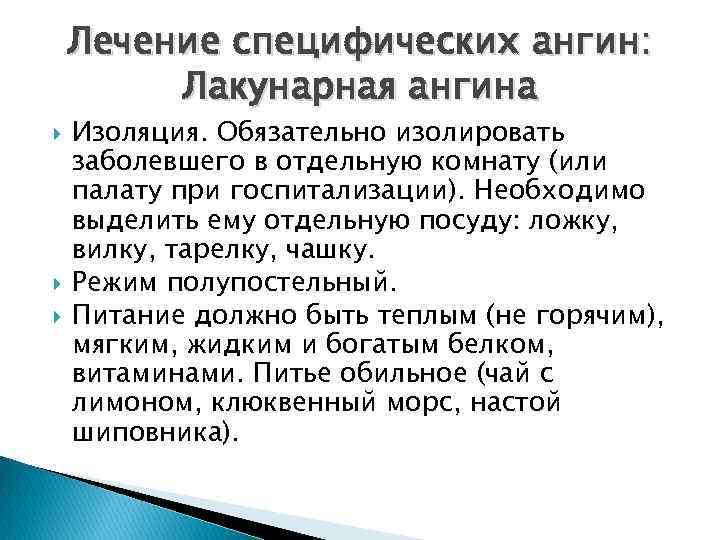

Процесс лечения лакунарной ангине

В первую очередь, пациенту назначается постельный и питьевой режим. Лакунарная ангина у взрослых лечится при помощи сульфаниламидных препаратов и ацетилсалициловой кислоты. Средства, понижающие температуру, необходимо принимать при температуре выше тридцати восьми градусов.

Не стоит забывать о том, что в основные правила лечения входит следующее.

- Соблюдение постельного режима. От прогулок на несколько дней нужно отказаться.

- Соблюдение питьевого режима. Если ребенок отказывается пить воду, то можно давать компоты, морсы и чаи. Особенно, это касается грудничков. Это позволит избежать обезвоживания организма.

- Сбалансированное и правильное питание. В период болезни пациента не стоит заставлять кушать. Но если больной не отказывается, то лучше давать супчики или различные овощные и фруктовые пюре.